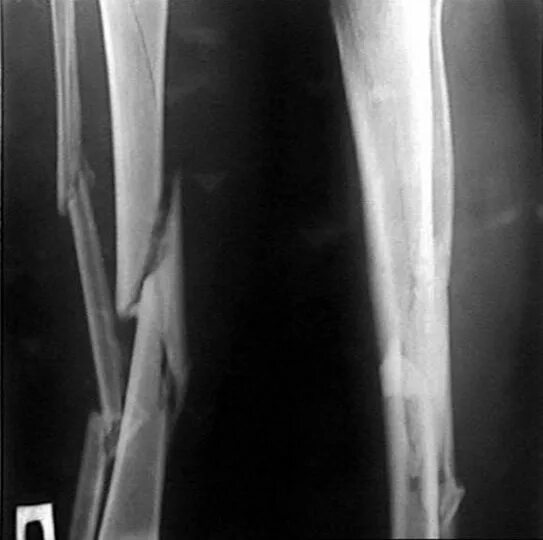

Оскольчатый перелом без смещения